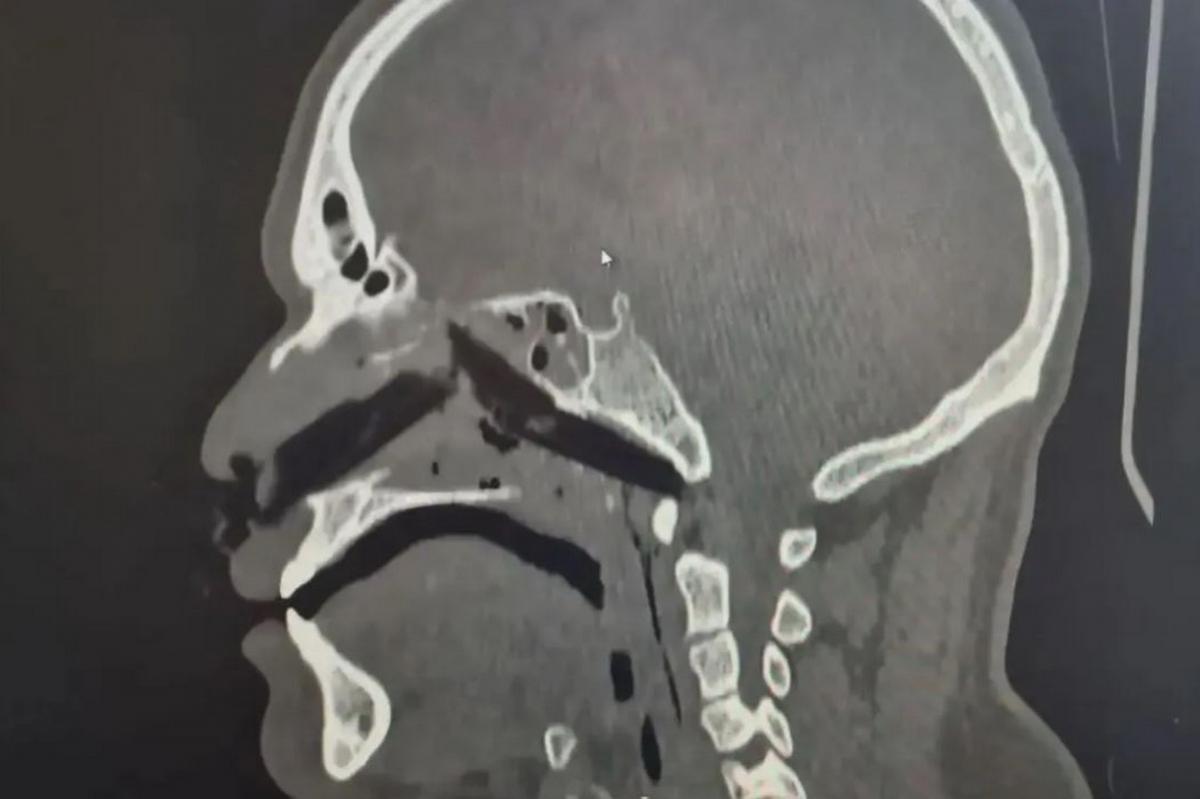

Как рассказали в министерстве здравоохранения области, более чем десятисантиметровая заноза пробила кожу и мышцы, достигнув носоглотки. Пострадавший не мог нормально дышать и испытывал сильную боль. Товарищи по цеху не стали медлить — бригада скорой помощи выехала мгновенно и прибыла на вызов спустя несколько минут.

Как объясняют представители учреждения, всё дело в физических свойствах дерева — в отличие от металла или пластика, инородный предмет моментально начал впитывать влагу со слизистых оболочек носа и разбухать прямо в теле пациента. Учитывая длину осколка и его анатомическое расположение, работать приходилось филигранно. Но профессионалы справились: щепка была извлечена целиком, медики сумели предотвратить опасность, когда она могла расколоться на части.